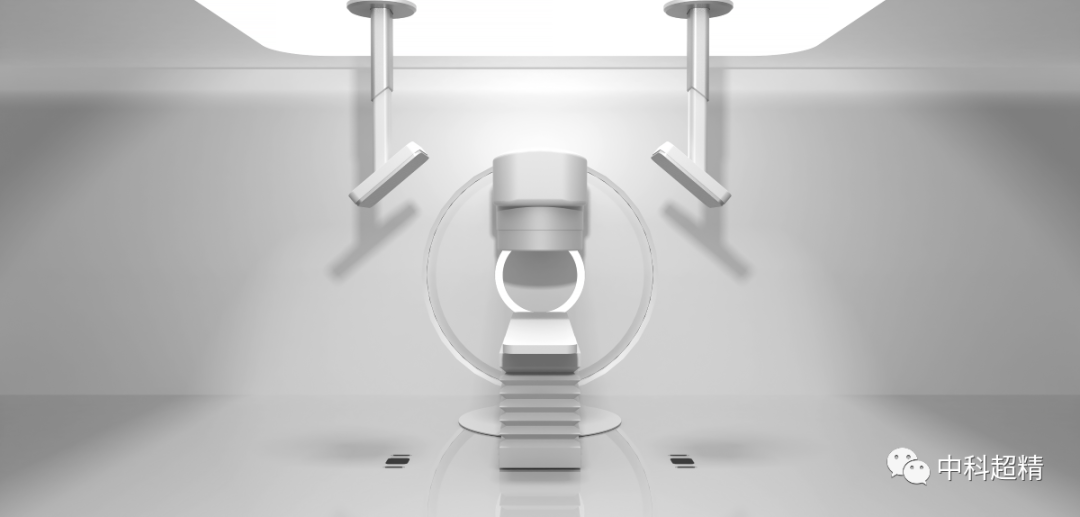

近日,中科超精(南京)科技有限公司(以下簡(jiǎn)稱“中科超精”)研發(fā)的“麒麟刀·木” X射線圖像引導(dǎo)系統(tǒng)(KylinRay-XGPS)獲國家藥監(jiān)局頒發(fā)的三類醫(yī)療器械注冊(cè)證,標(biāo)志著該產(chǎn)品正式登陸腫瘤放療市場(chǎng),成為創(chuàng)新實(shí)現(xiàn)放療精準(zhǔn)定位的自主品牌放療產(chǎn)品。

“麒麟刀·木” X射線圖像引導(dǎo)系統(tǒng)

(KylinRay-XGPS)

KylinRay-XGPS是面向腫瘤放射治療的圖像引導(dǎo)系統(tǒng),主要基于透視成像對(duì)腫瘤患者放射治療過程實(shí)施精確定位,是中科超精在精準(zhǔn)照射領(lǐng)域布局的另一重磅產(chǎn)品。該系統(tǒng)采用KV級(jí)透視成像和圖像智能配準(zhǔn)技術(shù),基于放射治療計(jì)劃以及三維CT圖像生成DRR圖像與采集投影圖進(jìn)行2D-3D圖像配準(zhǔn),精確探測(cè)出 6個(gè)自由度的擺位誤差,真正實(shí)現(xiàn)了對(duì)患者在每個(gè)分次的高質(zhì)量圖像引導(dǎo)。此產(chǎn)品可以獨(dú)立安裝,無需與直線加速器建立電氣連接,可適應(yīng)各種主流加速器型號(hào)以及不同結(jié)構(gòu)的機(jī)房,并幫助廣泛的用戶以最低的成本實(shí)現(xiàn)圖像引導(dǎo)的放射治療。